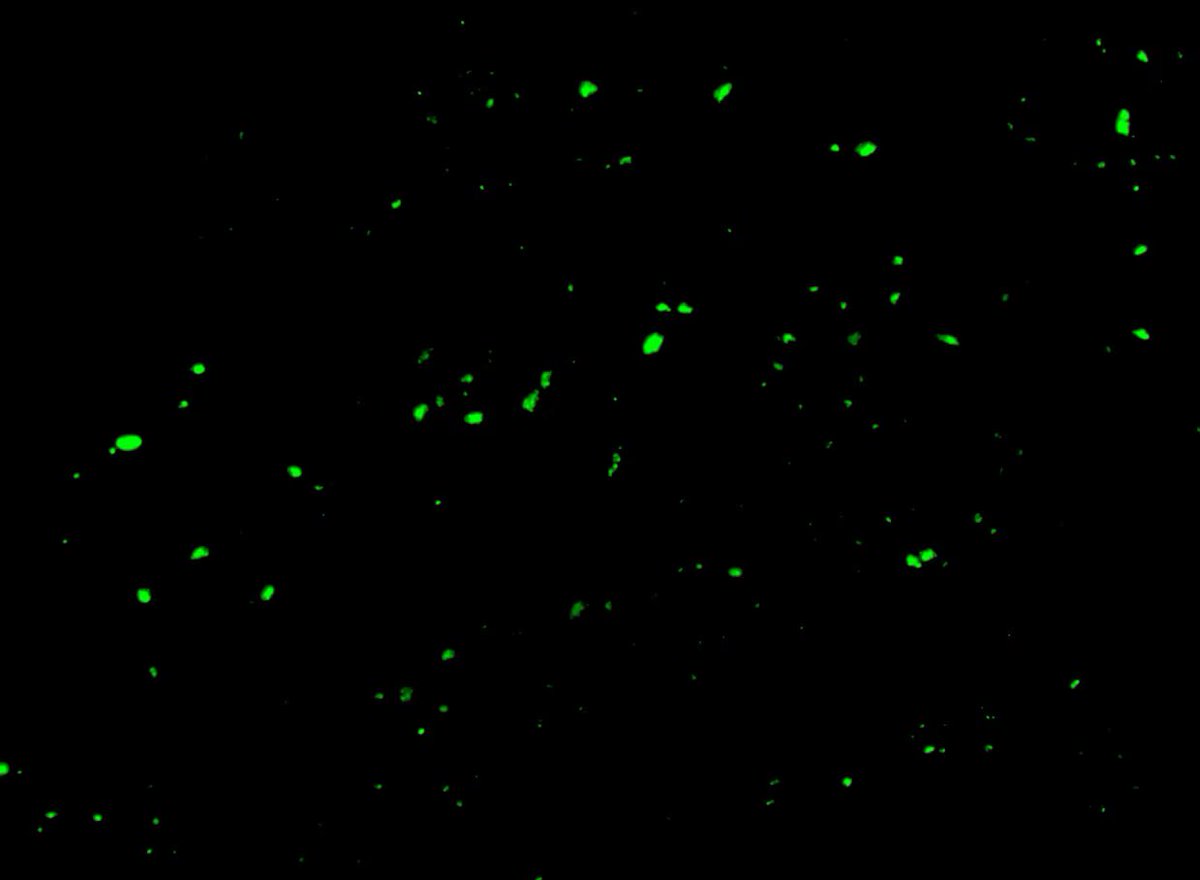

Seit mehr als zwei Jahren versuchen Wissenschaftler zu verstehen, warum Millionen von Menschen auf der ganzen Welt trotz Genesung von ihrer akuten COVID-19-Infektion unter anhaltenden Symptomen leiden. Sie haben mehrere Hypothesen aufgestellt, darunter das Vorhandensein von

Mikroklumpen - winzigen Blutgerinnseln, die Kapillaren verstopfen und möglicherweise den Blut- und Sauerstofffluss beeinträchtigen können. In einer Studie aus dem Jahr 2021 wiesen die Physiologin Etheresia Pretorius von der Universität Stellenbosch in Südafrika und ihre Kollegen

als erste darauf hin, dass Mikroklumpen mit diesem schwächenden Zustand, der als Long COVID bezeichnet wird, zusammenhängen könnten. In einer Folgestudie wiesen sie und ihre Kollegen nach, dass das SARS-CoV-2-Spike-Protein die Bildung solcher Gerinnsel auslöst, die der

körpereigene Prozess zur Auflösung von Blutgerinnseln nicht ohne weiteres aufzulösen scheint. Diese Erkenntnis hat einige Wissenschaftler in den Vereinigten Staaten dazu veranlasst, unter Anleitung von Pretorius Menschen mit Long COVID auf Mikroklumpen zu testen.

David Putrino, ein Wissenschaftler für Rehabilitation und Long COVID am Mount Sinai Health System, und seine Mitarbeiter sammeln Blutproben, um nach Mikroklumpen zu suchen. "Wir sind noch ganz am Anfang", sagt Putrino. "Wir haben bisher nur ein paar Dutzend Leute getestet." Aber

jede Probe von Patienten, die an Long COVID erkrankt sind hat solche Gerinnsel gezeigt. Im Moment sehen Putrino und sein Team einen Zusammenhang zwischen der Anzahl der Mikroklumpen auf einem Objektträger und dem Schweregrad der kognitiven Beeinträchtigung eines Patienten. Dazu

gehört die Fähigkeit, Emotionen zu regulieren, langfristige Lösungen für Probleme zu planen und zu erarbeiten oder Wege zu finden, mit sich verändernden Situationen in Echtzeit umzugehen. Das Forschungsteam entwickelt auch ein objektives Maß für Mikroklumpen. "Wir befinden uns

noch in einem sehr rudimentären Stadium", sagt Putrino. Einige Experten halten die Hypothese der Mikroklumpen zwar für plausibel, glauben aber, dass sie nur ein Teil des Puzzles von Long COVID sein könnte. Sie wünschen sich jedoch weitere Untersuchungen, die zeigen, wie diese

Gerinnsel zu den Symptomen von Long COVID beitragen und ob ihre Beseitigung zu besseren gesundheitlichen Ergebnissen führt. Wenn diese Mikroklumpen über längere Zeit bestehen bleiben, könnte der Körper Autoantikörper produzieren - Proteine, die unbeabsichtigt körpereigenes

gesundes Gewebe angreifen und zu schwächenden Störungen führen. "Es sind diese Menschen, um die wir uns besonders sorgen", sagt Etheresia Pretorius.